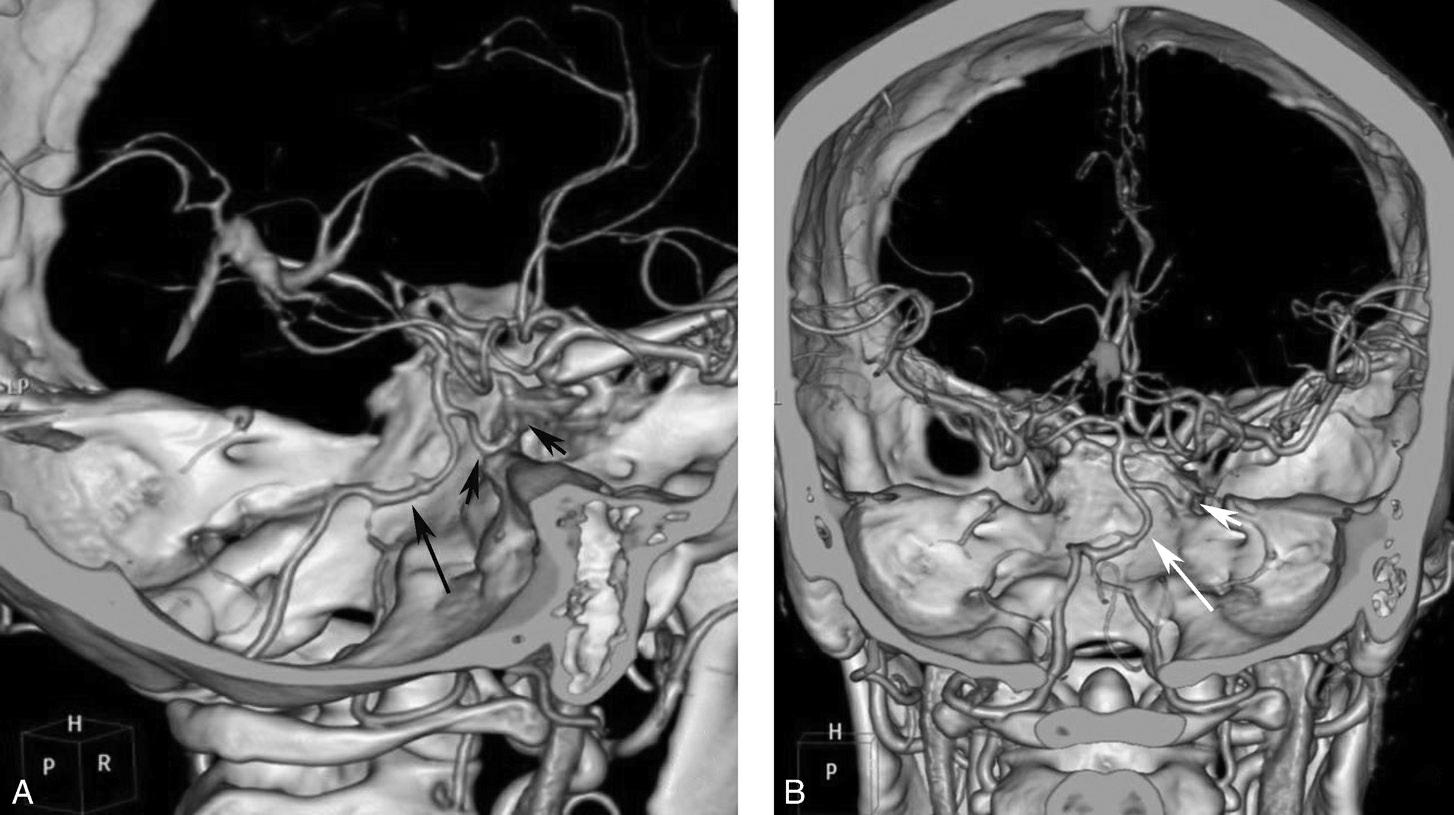

永存三叉动脉是颈内动脉海绵窦段与基底动脉之间的胚胎性吻合,为颈内动脉系统与椎基底动脉系统之间最常见的异常交通,是根据它伴行的颅神经而命名的。其他异常吻合包括永存听动脉、永存舌下动脉及永存寰前节间动脉(图1-2-79)。

图1-2-79 永存三叉动脉

A、B.异常吻合支沟通至右侧海绵窦(箭);基底动脉(长箭)